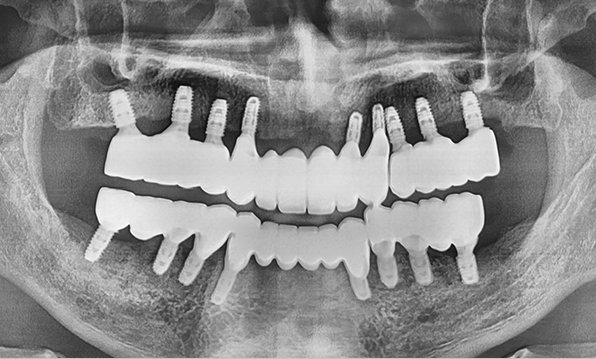

전체 임플란트

위 아래 치아가 정확하게 맞아야하는 고난이도 임플란트

임상 경험이 많은 숙련된 전문의의 섬세한 기술력이 중요합니다.

3D 디지털 진단을 통한 체계적인 계획

전체 임플란트는 위턱과 아래턱의 교합, 잇몸뼈의 상태 및

얼굴 변화 등 모든 것을 고려해 식립해야 합니다.

서울더자연치과는 3D 디지털 기술의 정밀 진단을 바탕으로

수술 계획을 세워 수술을 집도합니다.

치료기간 : 2021.04.12~2021.09.15